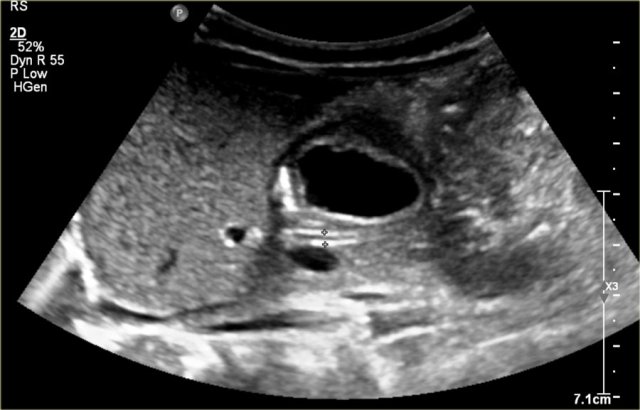

One-year-old boy was referred with a diagnosis of a cystic nephroblastoma.

Ultrasound detected a huge cyst in the middle of the abdomen.

When examined from the left flank with a high frequency linear array probe some parenchymal tissue was visible surrounding very dilated calyces. This is compatible with an extreme hydronephrosis.

At first it was thought that there were some solid parts in the cyst.

But when pressure was applied with the probe this proved to be debris.

MRI depicts the hydronephrosis with more overview.

The cause was a pyeloureteric stenosis.

The left kidney had 33% split renal function on renography.

A pyelum reconstruction was successfully performed.